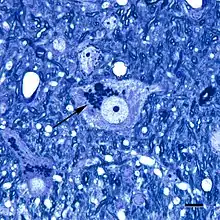

Micrograph showing a cluster of lipofuscin particles (arrow) in a nerve cell of the brain; toluidine blue stain; scale bar = 10 microns (0.01 millimeters)